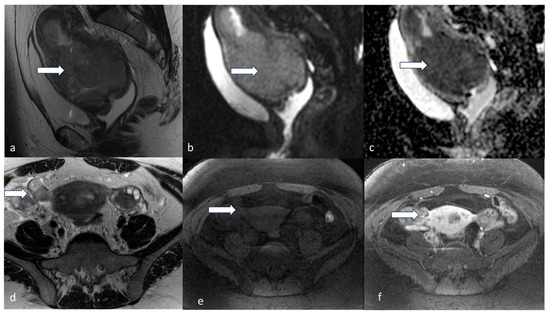

5.3. Magnetic Resonance Imaging (MRI)

- Maheshwari, E.; Nougaret, S.; Stein, E.B.; Rauch, G.M.; Hwang, K.-P.; Stafford, R.J.; Klopp, A.H.; Soliman, P.T.; Maturen, K.E.; Rockall, A.G.; et al. Update on MRI in Evaluation and Treatment of Endometrial Cancer. RadioGraphics 2022, 42, 2112–2130. [Google Scholar] [CrossRef] [PubMed]

- Neves, T.R.; Correia, M.T.; Serrado, M.A.; Horta, M.; Caetano, A.P.; Cunha, T.M. Staging of Endometrial Cancer Using Fusion T2-Weighted Images with Diffusion-Weighted Images: A Way to Avoid Gadolinium? Cancers 2022, 14, 384. [Google Scholar] [CrossRef] [PubMed]

- Nougaret, S.; Reinhold, C.; Alsharif, S.S.; Addley, H.; Arceneau, J.; Molinari, N.; Guiu, B.; Sala, E. Endometrial Cancer: Combined MR Volumetry and Diffusion-weighted Imaging for Assessment of Myometrial and Lymphovascular Invasion and Tumor Grade. Radiology 2015, 276, 797–808. [Google Scholar] [CrossRef]

- Nougaret, S.; Horta, M.; Sala, E.; Lakhman, Y.; Thomassin-Naggara, I.; Kido, A.; Masselli, G.; Bharwani, N.; Sadowski, E.; Ertmer, A.; et al. Endometrial Cancer MRI staging: Updated Guidelines of the European Society of Urogenital Radiology. Eur. Radiol. 2019, 29, 792–805. [Google Scholar] [CrossRef]